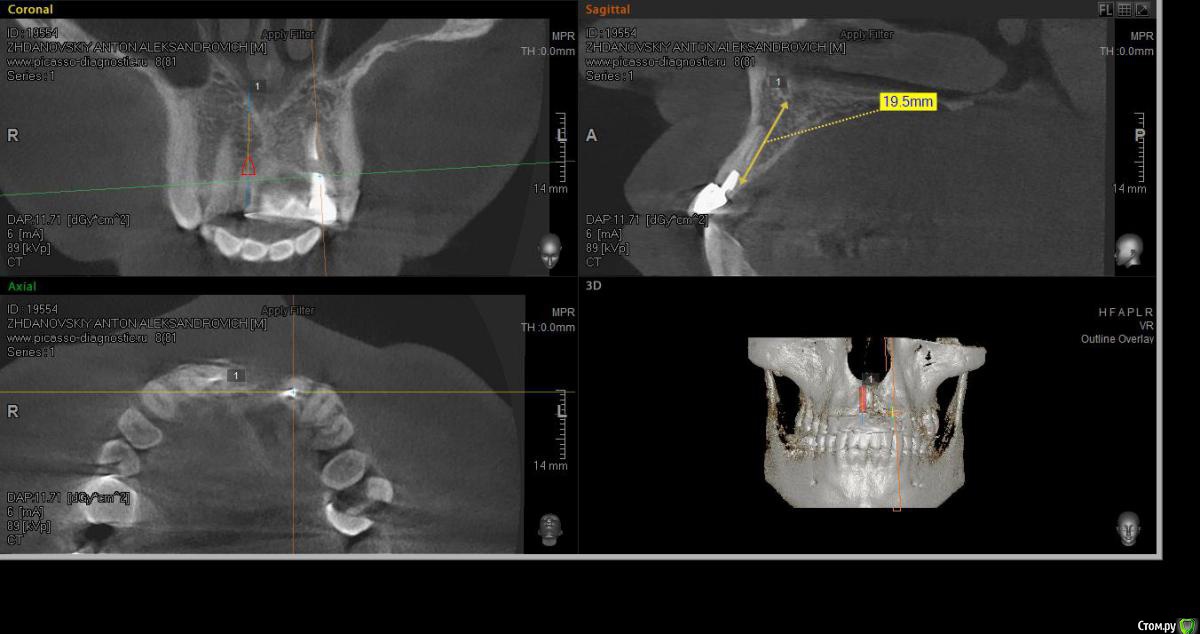

elen_only Опубликовано 1 августа, 2018 Поделиться Опубликовано 1 августа, 2018 Здравствуйте,коллеги! Помогите ,пожалуйста,неопытному имплантологу спланировать операцию. Пациент направлен ортопедом на удаление 11,22 зубов по поводу трещин корней. Биотип десны тонкий. Похоже,оставлен артефакт в области 21. Опыта одномоментной имплантации ,к сожалению, нет. Нервничаю.Хочу атравматично удалить 11,22 ,установить имплантаты с заглушками. Пациенту готовят сьемное на время. Через 4 месяца,поработать с десной. А корень попробовать достать через микроразрез,не отслаиваясь широко,такой опыт уже был. Подскажите,правильно ли я спланировала операцию? Или лучше сначала удалить корень а потом удалять зубы и имплантировать? Ссылка на комментарий

Irouil Опубликовано 1 августа, 2018 Поделиться Опубликовано 1 августа, 2018 Я тоже против съёмного, судя по Вашим срезам есть шансы на неплохой торк, так что, как по мне, мостик прямым методом. В идеале сразу трансплантат под понтик, но безопаснее и проще будет с этим поработать перед ортопедией - сможете спокойно снимать и моделировать овоид сколько душе будет угодно. В области 2.1, если пациента ничего не беспокоит, я бы не лез. Выводить на винтовую, рентген контроль имплантатов и корня раз в полгода/год Ссылка на комментарий

колесников Опубликовано 2 августа, 2018 Поделиться Опубликовано 2 августа, 2018 Свои 5 копеек вставлю. С одной стороны одномоментный малоинвазивная имплантация во фронтальной зоне с прогнозируемым эстетическим результатом -высший пилотаж и даже мелкая неудача, на поздних сроках, тяжело поддаётся корректировке,это надо понимать. Но с другой стороны,надо же когда то начинать.Касаемо вашего случая. 22 однозначно удалится с вестибулярной компактной пластинкой,вы должны иметь в запасе несколько вариантов закрытия этой проблемы с долгосрочным прогнозом. На мой взгляд более значительная проблема в зоне 21,после удаления 22 вероятно ткани подтянуться и сосочек 21-22 будет утрачен ,даже если вы сразу добавите объём в обл 21 и по началу будет казаться что все красиво получилось. Рекомендовал бы для атравматичноного удаления 22го ортодонтическую экструзию на неделю -самый простой вариант для вас . Сам бы наверно удалял с выделением щита. Еще вариант IDR. Другие способы считаю очень рискованными. И однозначно немедленная нагрузка. 3 1 Ссылка на комментарий